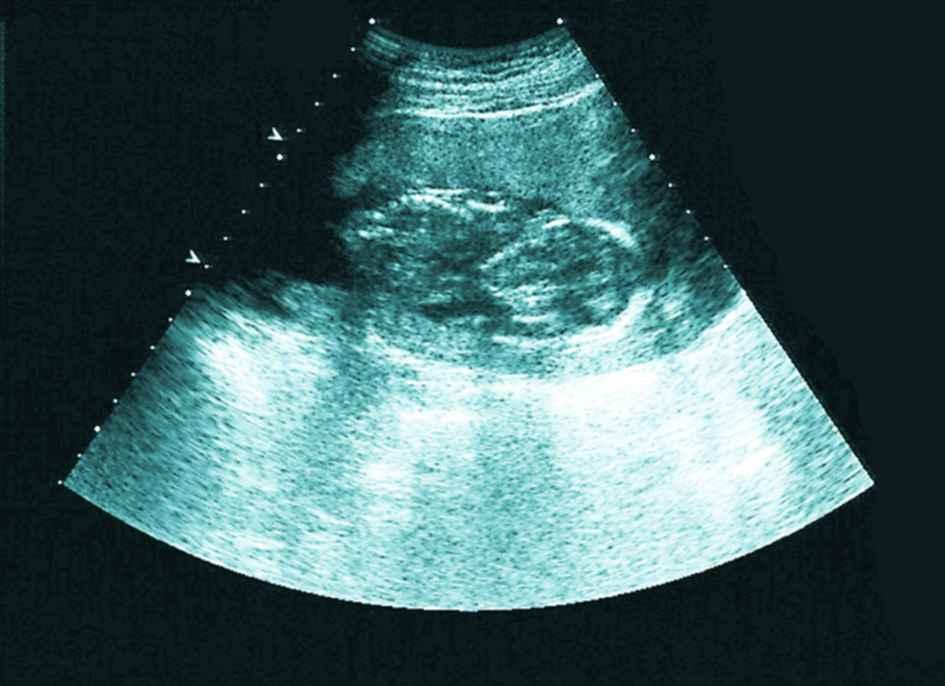

12月迟迟白带不拉丝,以为不会排卵了,到医院做了内诊和B超,又开消炎药,嘱咐我月经后通液或者造影。当时B超结果显示输卵管有优势卵泡16×14,于是回来安排功课了,没有避孕,后来几次避孕。

然而神奇的是,月经日居然测到了亲妈灰,但是颜色加深比较慢,第35天医院B超验血,没检查到孕囊,当时大夫说腹部超看不到宫外,弄得我特烦,跟他顶了几句嘴,血值hcg80不太理想,74小单位的孕酮,7天后hcg700多,又过两天hcg1044,孕酮38,也就是说在第45天,孕酮下降,于是主动B超,结果显示内膜比第35天时的薄了,且回声不均匀,宫内外都没有孕囊,大夫说孕酮下降估计是胎停,因为看不到宫内所以不给保胎。

等到能看到宫内时hcg2800多,孕酮10多一点,被宣布胎停。

孕早期,hcg数值不好,也看不到孕囊,那也不用急躁,注意看B超单,如果内膜不均匀应该是宫内孕,我在网上查阅过有姐妹这么说的,这也是我判断我不是宫外的依据。